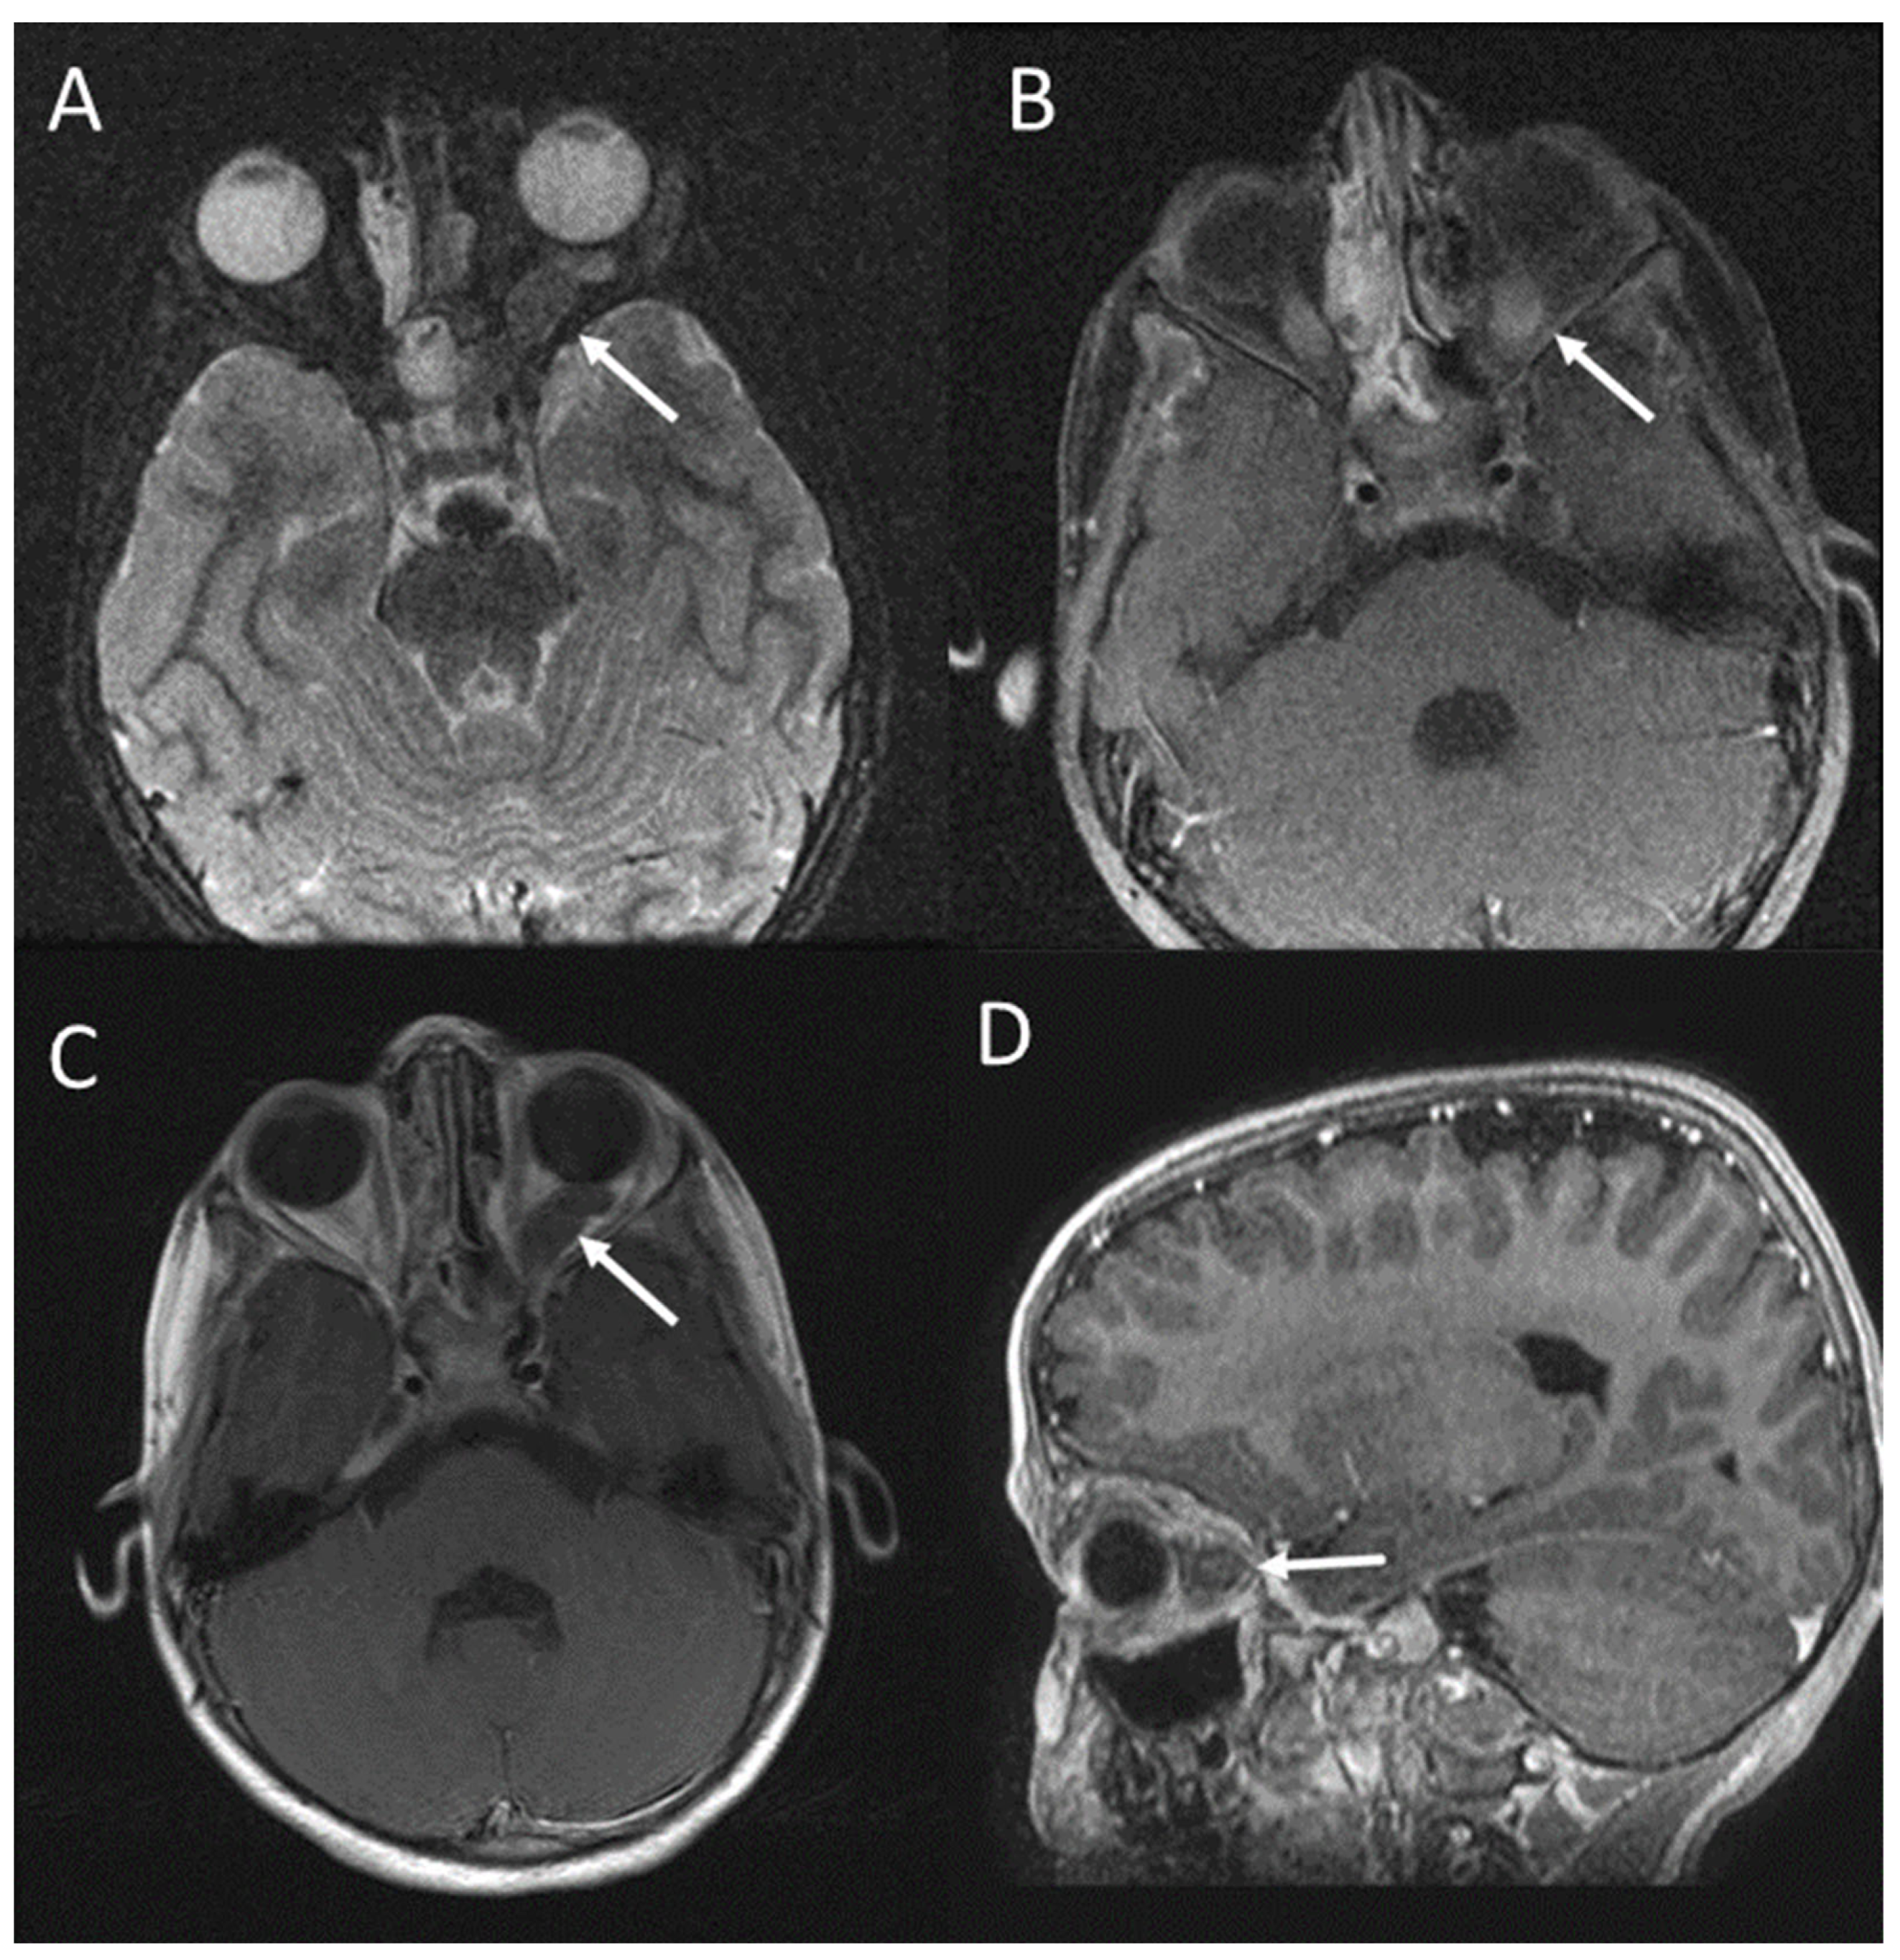

2.1. Visual Pathway Lesions

| Visual pathway lesions (optic pathway gliomas) | 5–15% | Enlargement of optic nerves or chiasma (diameter greater than 3.9 mm); |

| On T2-weighted images: compact low signal core with higher intensity circumferential component; | ||

| On T1-weighted images: isointense signal, with enhancement after gadolinium administration. | ||